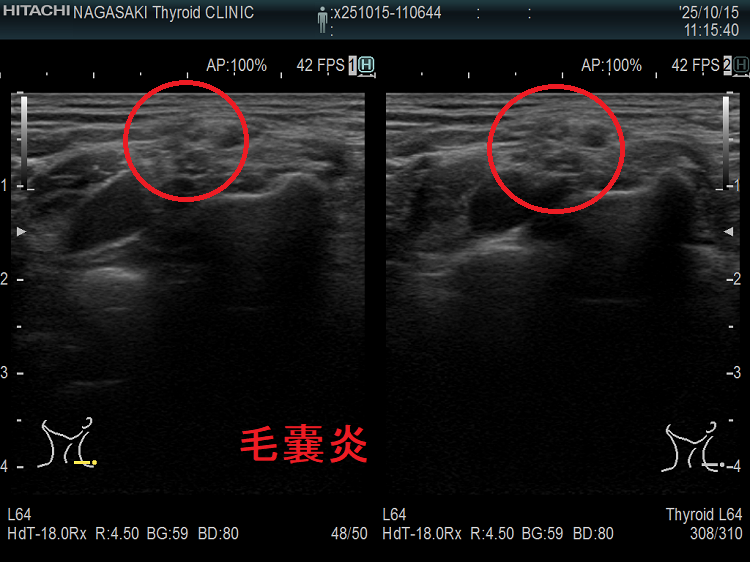

首の腫瘤・しこり・腫れ、甲状腺と思っても頸部軟部腫瘍(脂肪腫・脂肪肉腫・血管脂肪腫・粉瘤・パラガングリオーマ・ユーイング肉腫・滑膜肉腫)

首の腫瘤・しこり・腫れ、甲状腺と思っても、甲状腺超音波エコー検査で見ると頸部軟部腫瘍[頚部神経線維腫・神経鞘腫・脂肪腫・脂肪肉腫(急激に増大)・筋腫・血管脂肪腫(副腎皮質ステロイドの長期間使用,糖尿病で発症。痛みを伴う)・粉瘤(アテローマ、アテローム)[皮脂がたまって腫瘍化。痛み無し]・パラガングリオーマ(傍神経節腫)(交感神経由来はカテコラミン過剰産生、副交感神経由来はホルモン産生しない)・ユーイング肉腫・滑膜肉腫]の事も。

粉瘤(アテローマ、アテローム):皮脂がたまって腫瘍化したものです。痛みはありません。

写真の様に、甲状腺の真上にあると、甲状腺腫瘤と思って、長崎甲状腺クリニック(大阪)を受診される方があります。